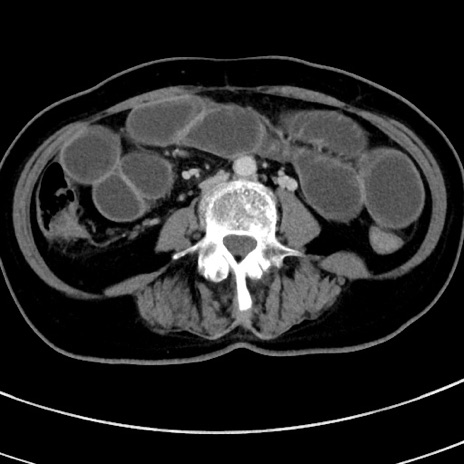

症例9(横断像)

【症例】 60歳代女性

【主訴】むかつき、みぞおちの痛み

【現病歴】3日前よりむかつきがあり、食事がとれない。

【既往歴】糖尿病

【身体所見】発熱なし、心窩部圧痛軽度あるも、腹膜刺激症状なし。

【データ】WBC 7400、CRP 1.92